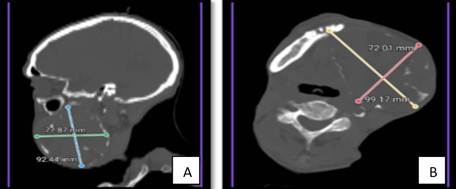

3. Imaging Study (Computed Tomography - CT): The facial CT scan revealed an osteolytic, expansive, and multiloculated lesion with well-defined margins, completely occupying the body and ascending ramus of the left hemimandible, with dimensions of 7.2 x 9.9 cm in the axial plane and 7.8 x 9.2 cm in the coronal plane (Figures 2A and 2B). No pathological lymphadenopathy or invasion of adjacent soft tissues was evident, but there was bone destruction exceeding 50% of the mandible.

Figure 2: CT scans (A: sagittal, B: axial) showing the multiloculated osteolytic lesion in the left mandible.